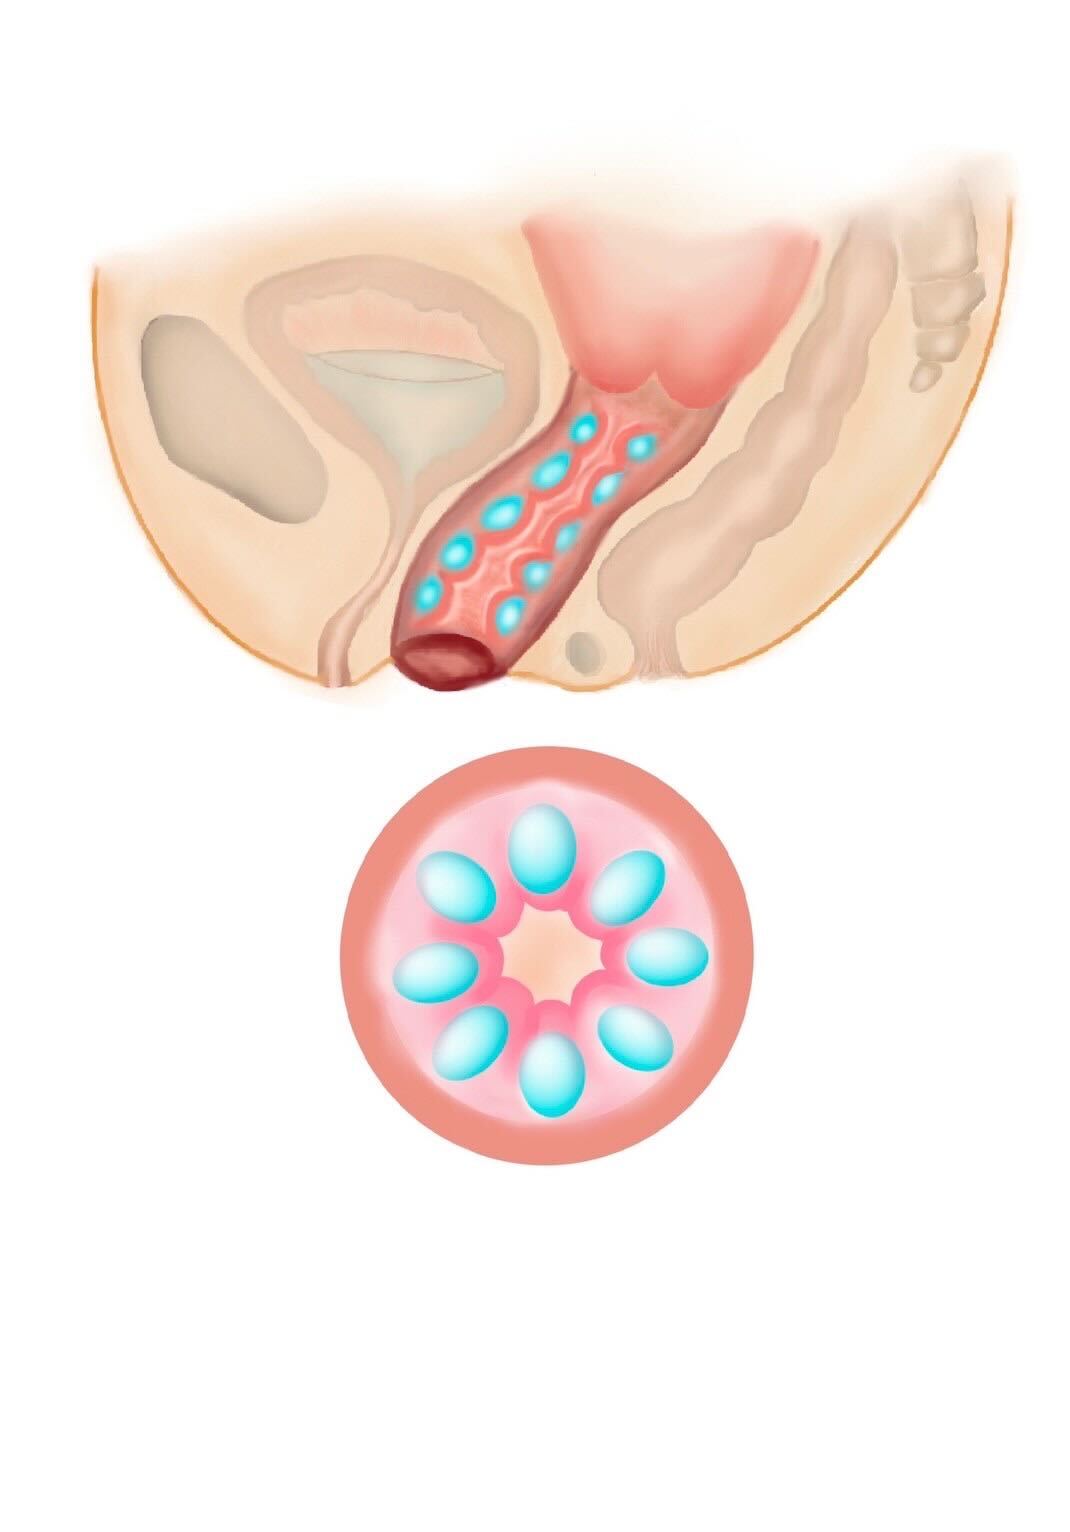

他にもヒアルロン酸注入や再生治療、レーザーなどの治療もありますが、腟壁縮小手術、腟括約筋縫縮術はあらゆる治療の中で最も効果の高い治療になります。腟壁縮小手術では、産後に緩んでしまった腟壁を腟の奥から切開し縮小します。腟周辺の筋肉を縮小縫合し、新たに腟のヒダを形成することが可能です。

また同時に入り口付近にある腟括約筋を縫縮すると、入り口から腟の奥まで縮小され、高い効果が得られます。 腟は直腸に接するようにすぐ前に位置しますので、繊細な作業を要し、高い技術が必要です。

加齢や出産が原因で低下した膣圧を改善する治療です。ヒアルロン酸を注入する部位や量を変えることで、膣内の好きな部位を狭くし自由に膣圧を高めることが可能です。治療直後より効果が実感できます。性行為時の満足度を高めたり、女性として自信が持てたり、尿漏れを改善するなどの効果があります。当院では、膣治療を専門的に行なっているため、お悩みに合わせたカスタム注入が可能です。 ヒアルロン酸は少しずつ体内に吸収され、1.2年でなくなりますので、効果を持続させたい方は追加の注入が必要になります。 効果を持続させたい方は膣内の脂肪注入をご検討ください。 みみず千匹、たこつぼ、きんちゃく、かずのこ天井など、ご希望を伺うことが可能です。

膣内に上下にヒアルロン酸を注入し、パートナー共に性行為時の感度を高めることが可能です。